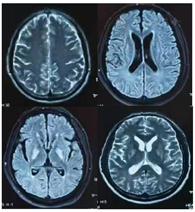

头颅MRI+DWI+SWI(2022年7月26日):双侧基底节区、放射冠小血管闭塞性脑梗塞可能;脑白质变性;双侧苍白球区对称性异常信号改变(图1)。